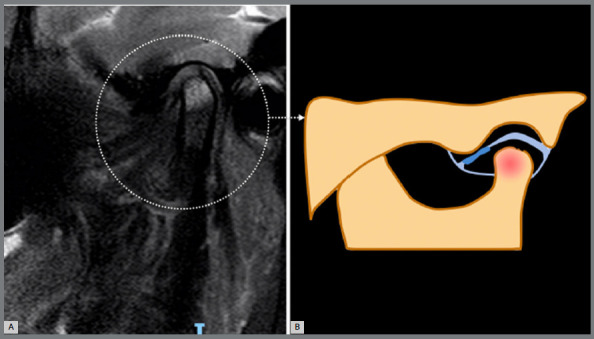

导言:骨关节炎(OA)是一种渐进性退行性疾病,以软骨逐渐退化、软骨下骨重塑、滑膜炎和慢性疼痛为特征。这种疾病会影响各种大小关节,包括颞下颌关节(TMJ)。然而,由于临床和影像学上的异质性,治疗 OA,尤其是阻止或减少疾病进展具有挑战性。越来越多的学者认为,这种异质性涉及不同的表型或亚群,可通过疾病的病理生理学和结构表现的差异来辨别。即使在颞下颌关节内,这些表型也可能显示出不同的临床特征、实验室参数、生化标志物和成像标准。最近的研究提出将核磁共振成像作为颞下颌关节 OA 的参考标准,强调其与组织病理学变化高度一致。基于核磁共振成像的表型为了解疾病进展和治疗反应提供了一条很有前景的途径,有可能为预后和治疗计划提供有价值的见解:本文介绍了ROAMES-TMJ(颞下颌关节骨性关节炎MRI快速合格评分),用于评估颞下颌关节OA临床试验的结构合格性。

Introduction: Osteoarthritis (OA) is a progressive degenerative disease characterized by the gradual degradation of cartilage, remodeling of subchondral bone, synovitis, and chronic pain. This condition impacts various large and small joints, including the temporomandibular joint (TMJ). However, addressing OA, particularly in impeding or reducing disease progression, is challenging due to its clinical and imaging heterogeneity. Authors are increasingly suggesting that this heterogeneity involves different phenotypes or subpopulations, discernible by variations in the disease's pathophysiology and structural manifestations. Even within the TMJ, these phenotypes may display distinct clinical features, laboratory parameters, biochemical markers, and imaging criteria. Recent research has proposed MRI as a reference standard for TMJ OA, highlighting its substantial agreement with histopathological changes. MRI-based phenotypes offer a promising avenue for understanding disease progression and treatment response, potentially providing valuable insights for prognosis and treatment planning.

Objective: This article introduces the ROAMES-TMJ (Rapid OsteoArthritis MRI Eligibility Score for TMJ) to assess the structural eligibility of individuals for inclusion in TMJ OA clinical trials.